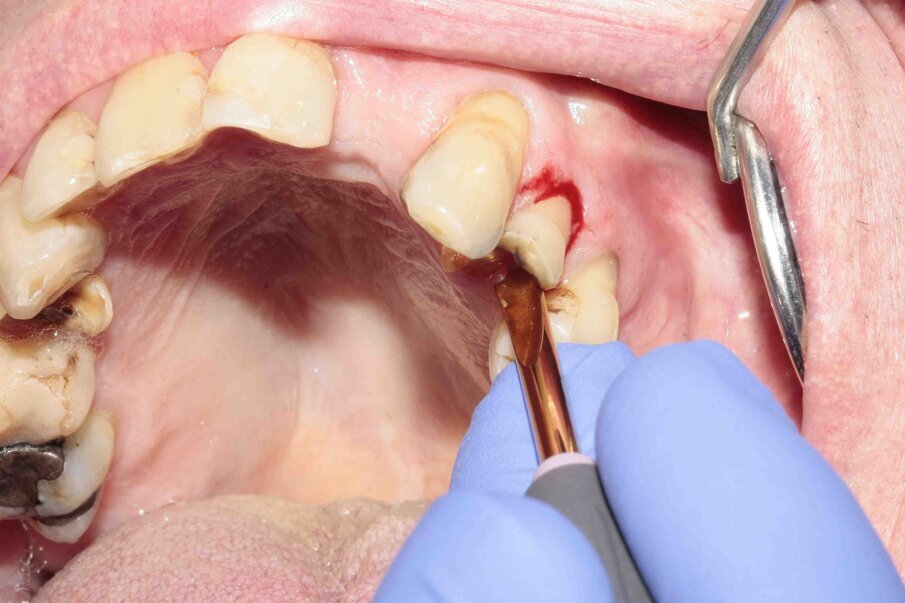

Fig. 9: During luxation, the palatal root was partially fractured while in the alveolus.

Figs. 10–12: The fractured root was carefully luxated with Luxator P1 and Luxator L3S.